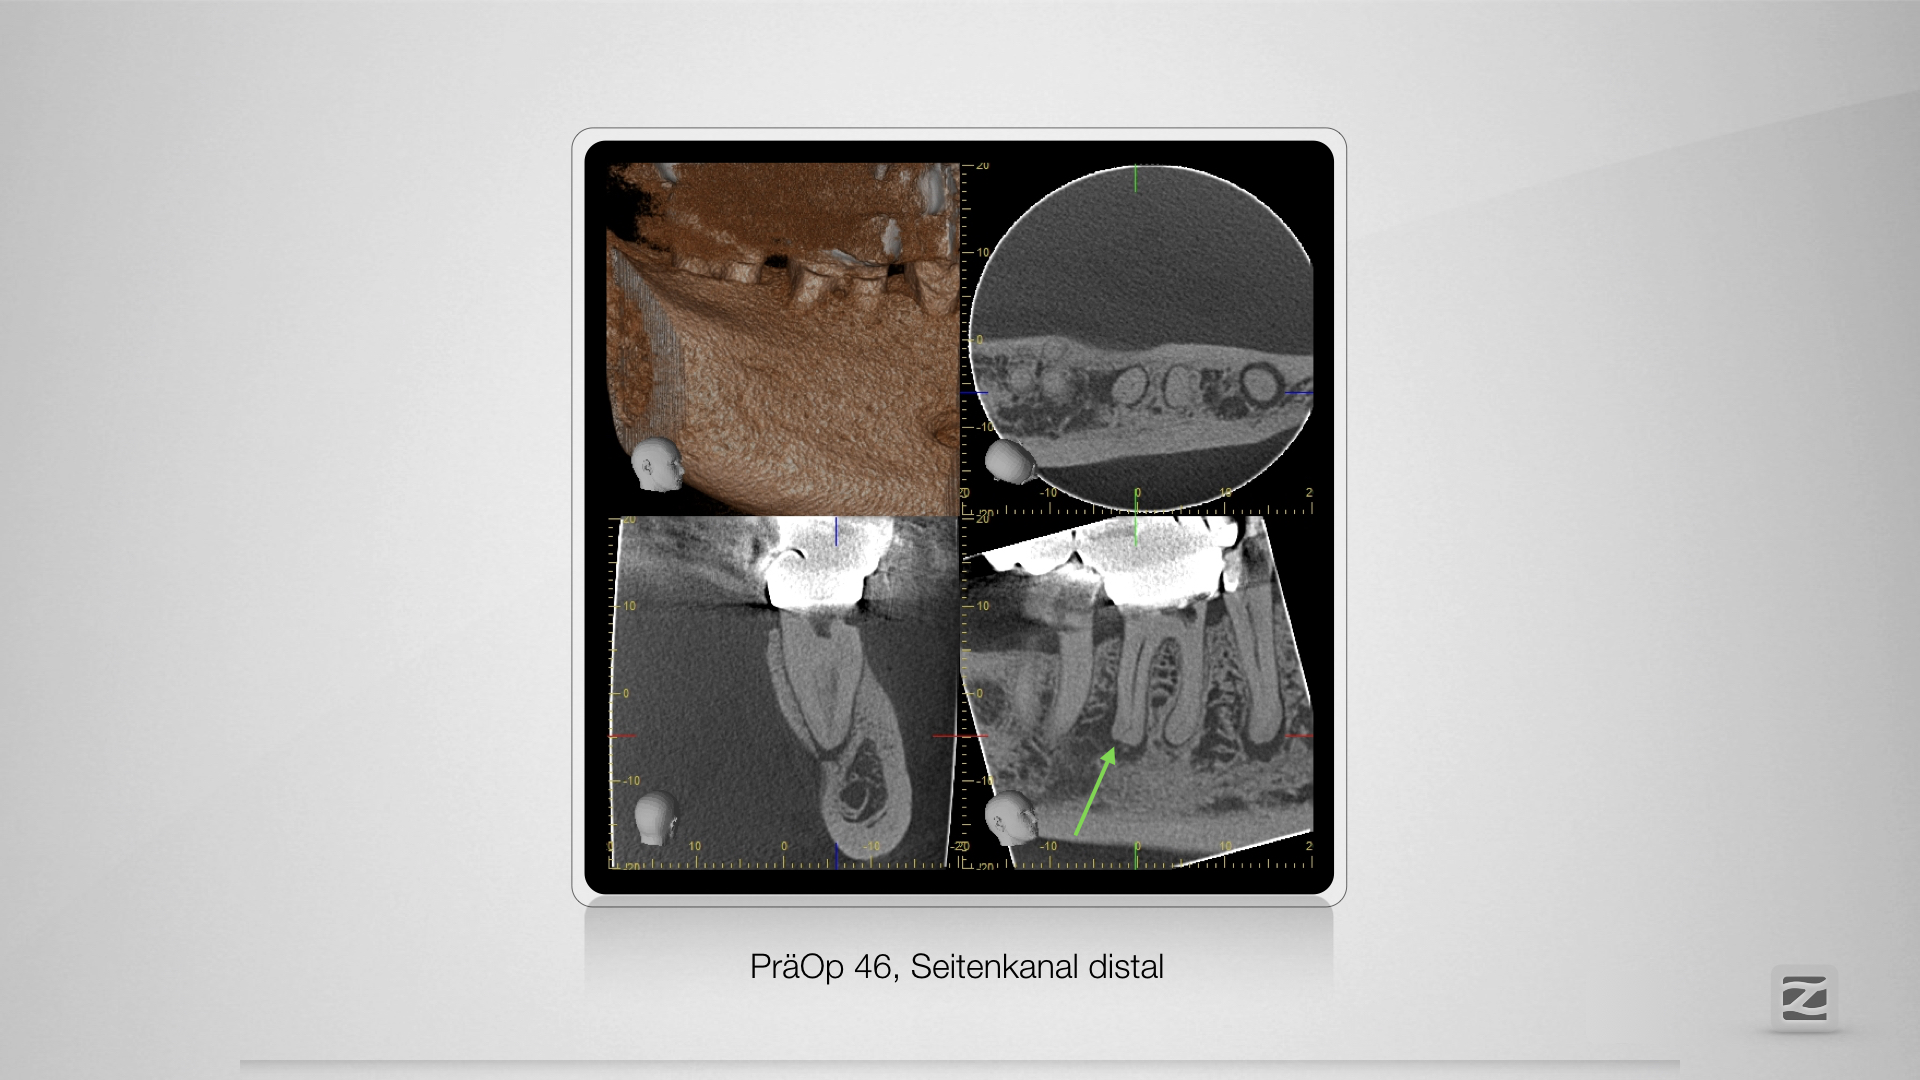

46D.007

Zugang, Zugang, Zugang.